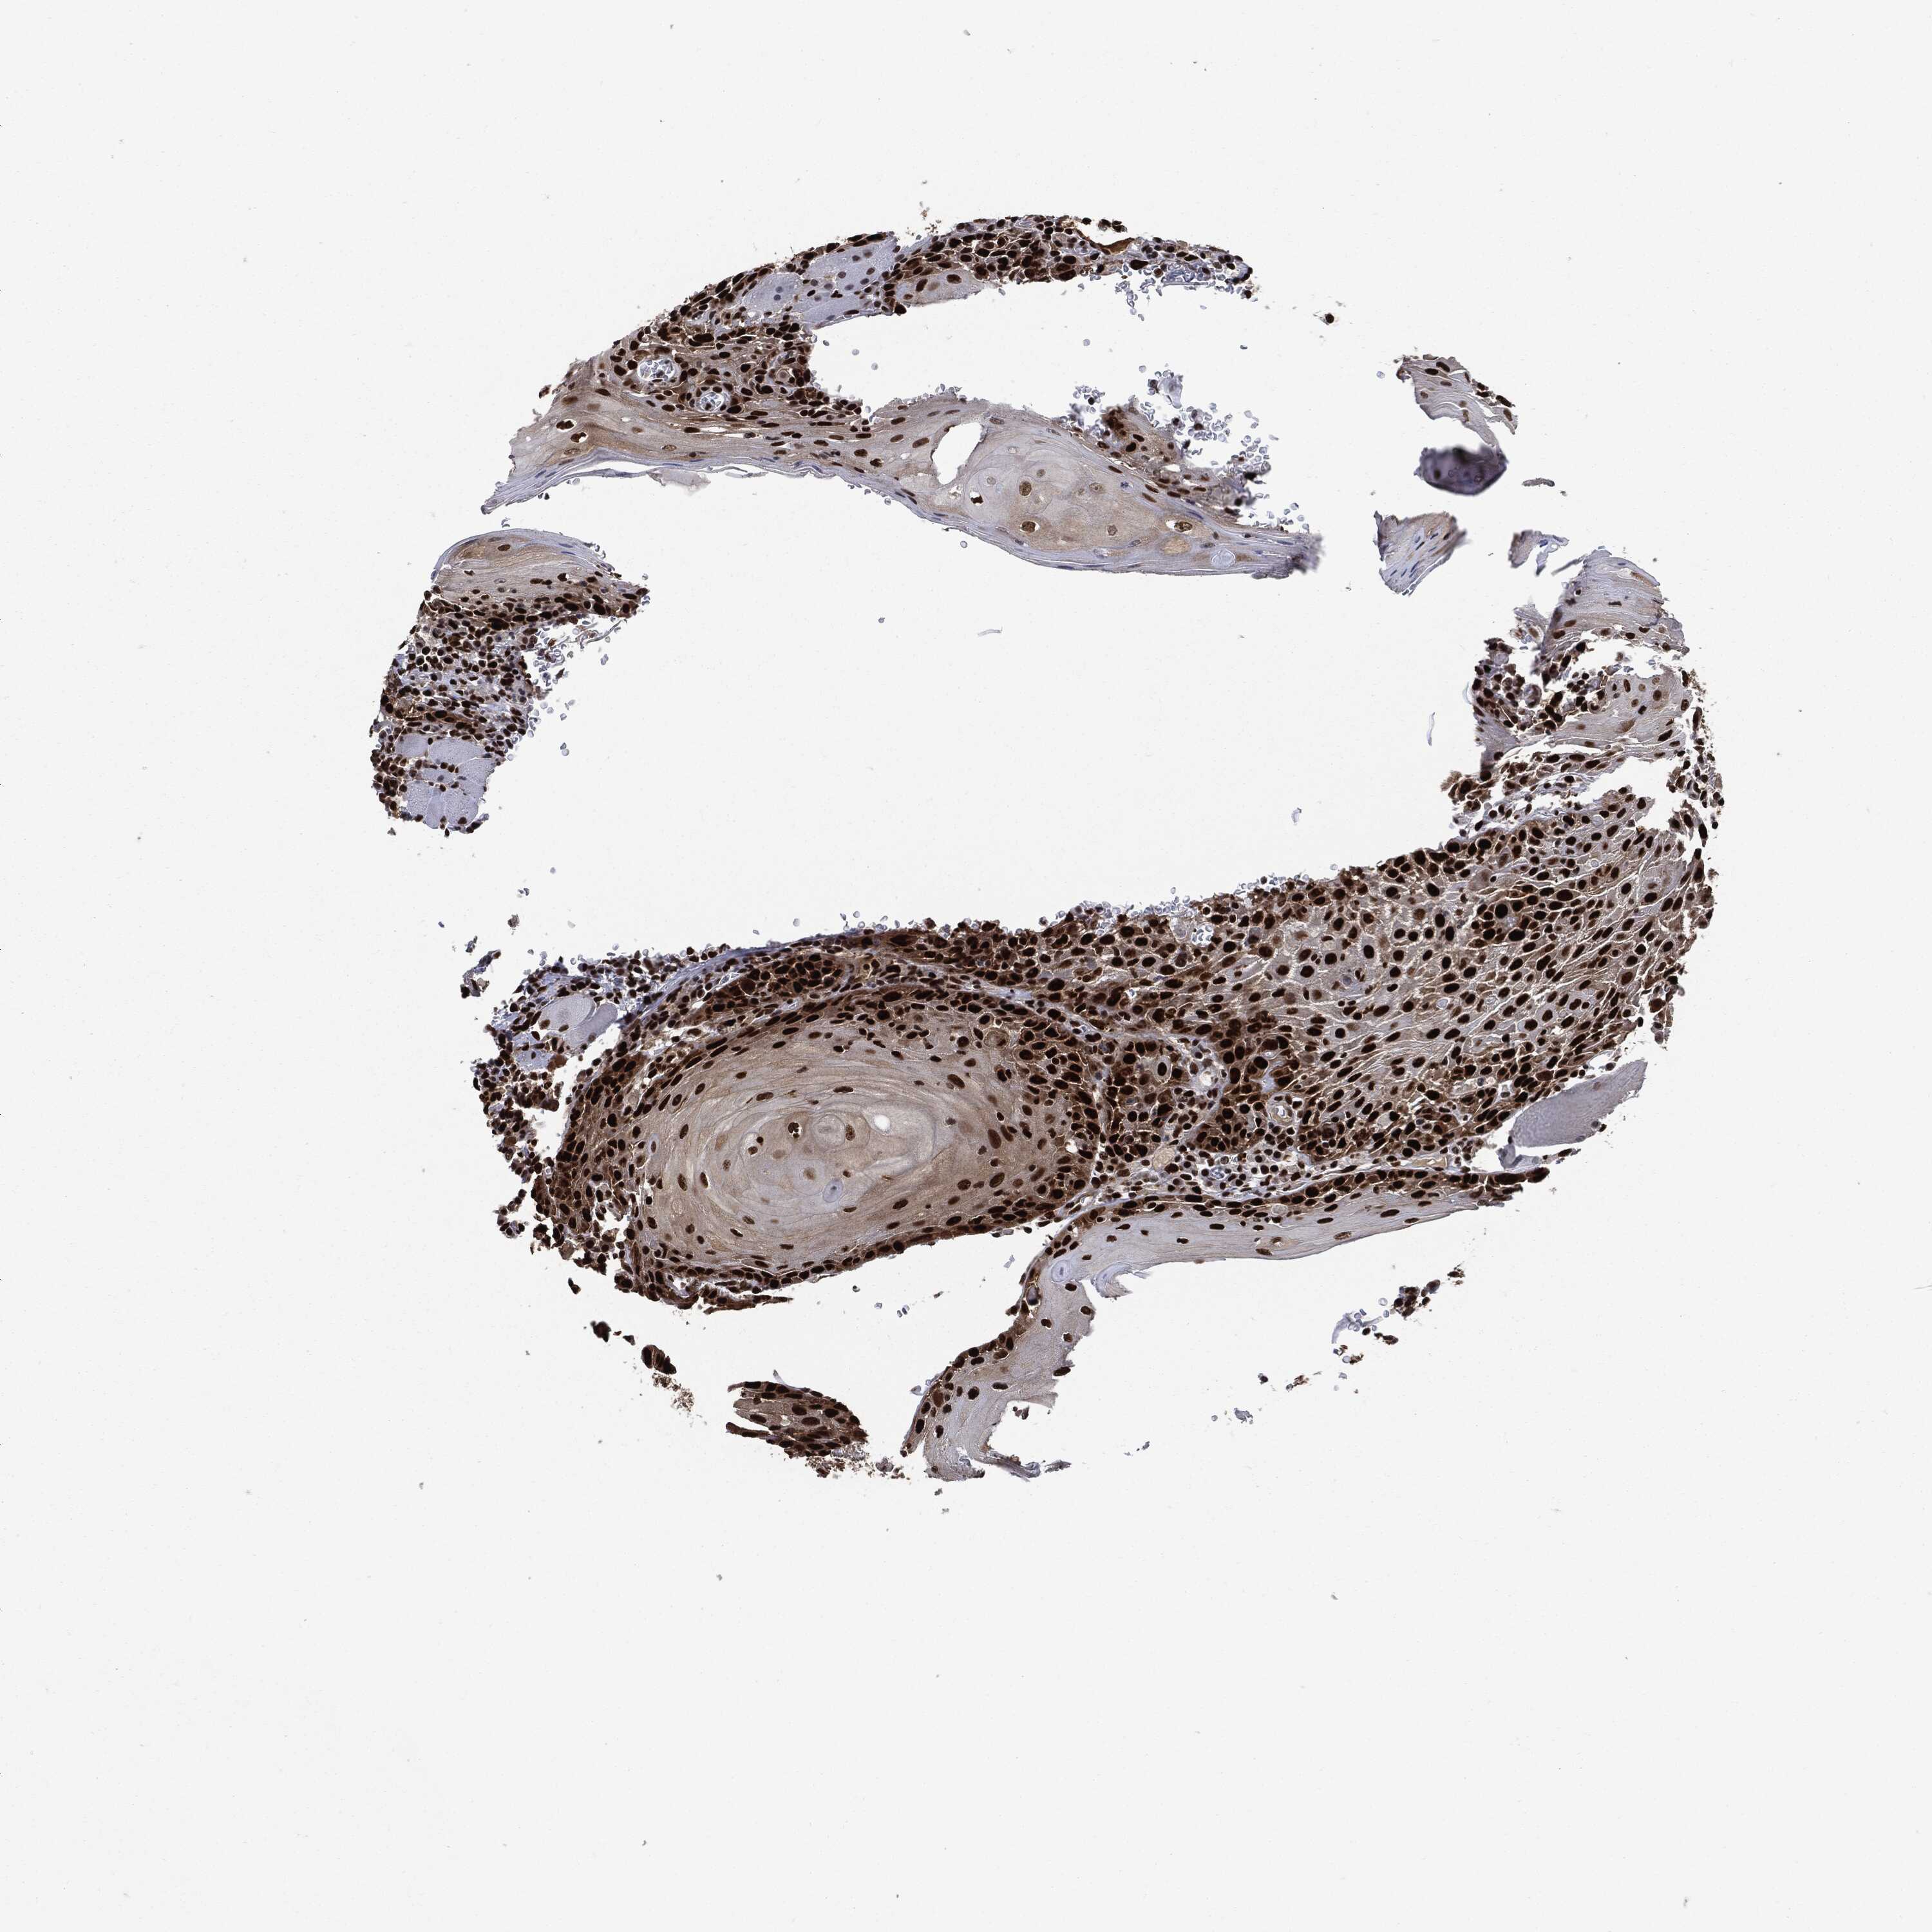

HEAD AND NECK CANCER - Protein expressioni

A mouse-over function shows sample information and annotation data. Click on an image to view it in a full screen mode. Samples can be filtered based on level of antibody staining by selecting one or several of the following categories: high, medium, low and not detected. The assay and annotation is described here.

Note that samples used for immunohistochemistry by the Human Protein Atlas do not correspond to samples in the TCGA dataset.

Antibody stainingi

Antibody staining in the annotated cell types in the current human tissue is reported as not detected, low, medium, or high, based on conventional immunohistochemistry profiling in selected tissues. This score is based on the combination of the staining intensity and fraction of stained cells.

Each image is clickable and will lead to virtual microscopy that enables deeper exploration of all samples and also displays staining intensity scores, fraction scores and subcellular localization as well as patient and tissue information for each sample.

HPA030521

HPA030522

HPA030523

CAB000148

CAB080240

CAB080241

CAB080242

Staining

High

Medium

Low

Not detected

Intensity

Strong

Moderate

Weak

Negative

Quantity

>75%

75%-25%

<25%

None

Location

Nuclear

Cytoplasmic/membranous

Cytoplasmic/membranous,nuclear

Squamous cell carcinoma, NOS

Squamous cell carcinoma, metastatic, NOS

Adenocarcinoma, NOS